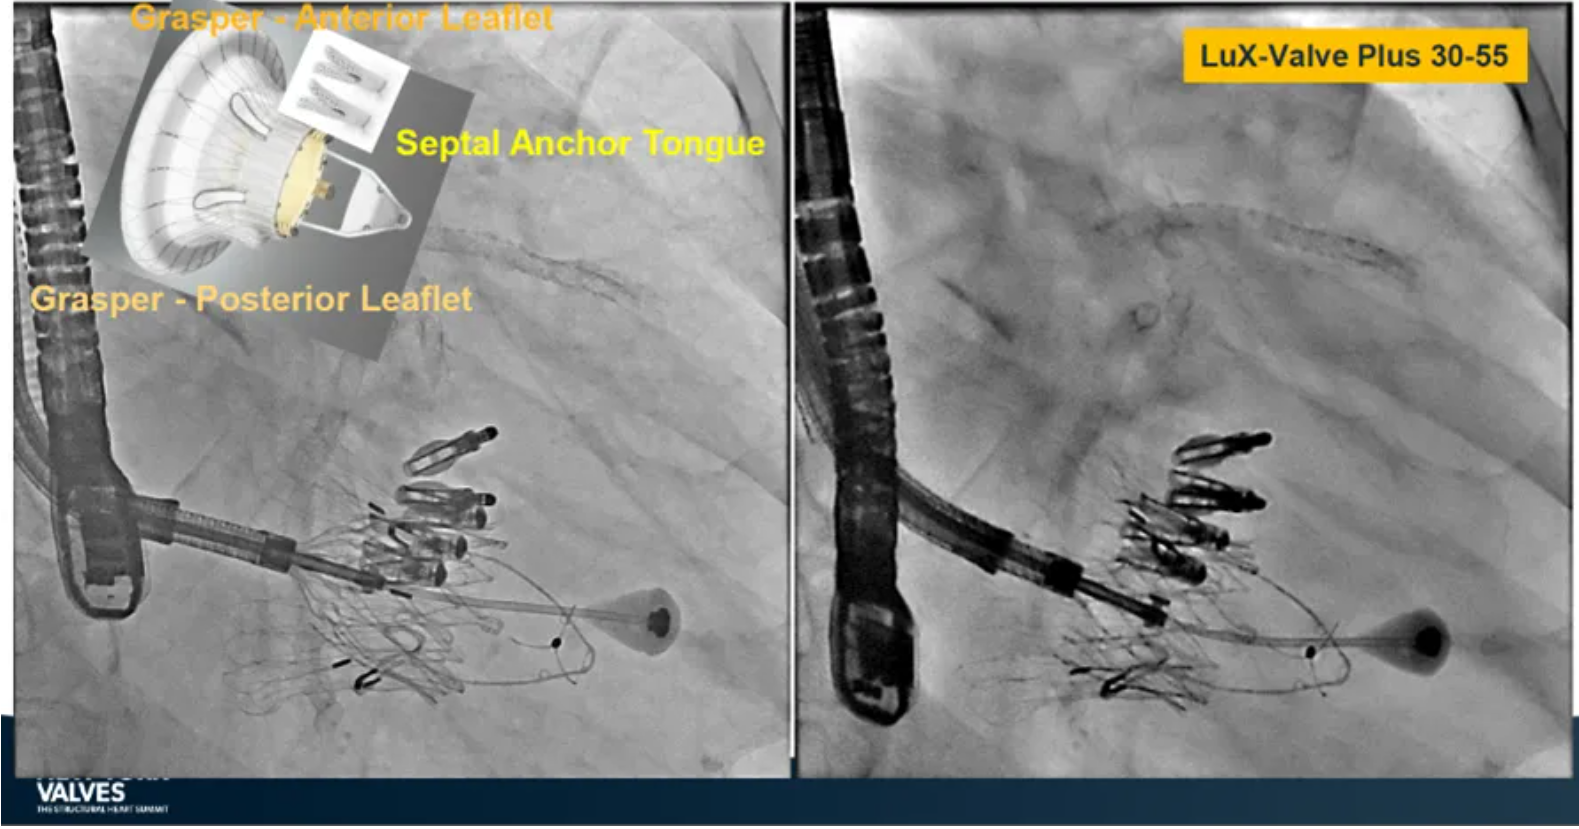

Granada教授表示,LuX-Valve Plus是一款不依賴于徑向支撐力固定的多功能TTVR器械,它的創(chuàng)新設(shè)計(jì)(室間隔錨定和瓣葉夾持件)提供了多樣的固定和穩(wěn)定技術(shù)。多中心臨床試驗(yàn)研究TRAVEL II 展現(xiàn)了LuX-Valve Plus的安全性和有效性,能實(shí)現(xiàn)較短的器械操作時(shí)間,較低的復(fù)合事件發(fā)生率,并在6個(gè)月期時(shí)顯著降低三尖瓣反流等級(jí),以及帶來(lái)心功能和生活質(zhì)量等指標(biāo)上的明顯改善。

隨后在2024年紐約瓣膜會(huì)上,Hausleiter教授再次提及LuX-Valve Plus,并介紹到對(duì)于不適合做T-TEER術(shù)式的患者也是適用的,并且能夠擴(kuò)大治療方式的選擇,例如瓣口接合有較大缺陷和超大瓣環(huán)的患者,以及超聲影像質(zhì)量較低不適合夾子術(shù)式等情況。Hausleiter教授表示LuX-Valve Plus展現(xiàn)了優(yōu)異的的早期臨床表現(xiàn)。

來(lái)自法國(guó)波爾多大學(xué)醫(yī)院(CHU de Bordeaux, Bordeaux, France)的Thomas Modine教授在2024紐約瓣膜會(huì)上介紹到針對(duì)目前三尖瓣反流臨床上的痛點(diǎn),包括大瓣環(huán)、起搏器或者心臟除顫器ICD導(dǎo)線的影響、依賴術(shù)中影像,以及術(shù)后起搏器的植入等,LuX-Valve Plus都能夠提供良好的解決方案。他在最后總結(jié)道,LuX-Valve Plus創(chuàng)新的設(shè)計(jì)能夠有效降低術(shù)后的并發(fā)癥,例如起搏器植入率和血栓的形成。同時(shí),TRAVEL II 研究的6個(gè)月期數(shù)據(jù)也體現(xiàn)了產(chǎn)品較短的器械操作時(shí)間,較低的復(fù)合事件發(fā)生率,顯著改善的心功能和生活質(zhì)量,以及能夠跟術(shù)前就已經(jīng)存在的起搏器導(dǎo)線兼容的優(yōu)勢(shì)。

來(lái)自中國(guó)上海復(fù)旦大學(xué)附屬中山醫(yī)院的魏來(lái)教授在2024年臺(tái)北瓣膜高峰論壇上分享了他使用LuX-Valve Plus治療三尖瓣反流的經(jīng)驗(yàn)。魏來(lái)教授闡述道,隨著療法演變,目前全球市場(chǎng)有以LuX-Valve Plus及其他產(chǎn)品為代表的經(jīng)導(dǎo)管三尖瓣介入置換系統(tǒng),逐漸成為重度三尖瓣反流的一線治療方案。他介紹到,LuX-Valve Plus創(chuàng)新的室間隔錨定和經(jīng)頸靜脈入路的方式,能夠帶來(lái)安全穩(wěn)定的錨定效果及較短的輸送行程;其可調(diào)彎的輸送系統(tǒng)能保證同軸性,從而快速和安全地將人工瓣膜送達(dá)目標(biāo)手術(shù)區(qū)域,有效降低入路周邊解剖組織并發(fā)癥及術(shù)中出血風(fēng)險(xiǎn)。